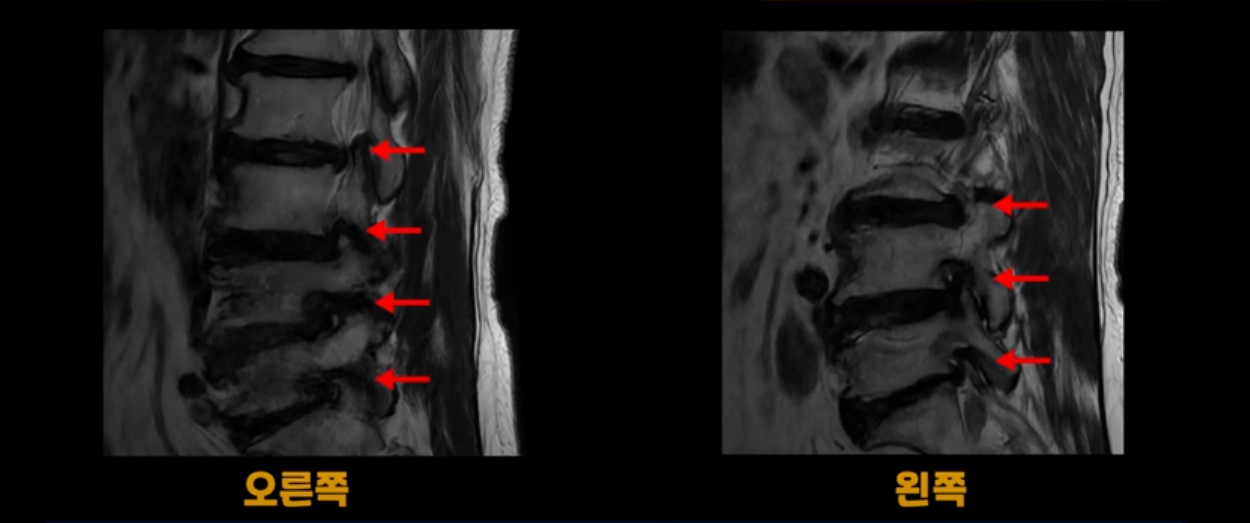

이렇게 모두 다 심하게 막히는 경우는 드문데요. 또한 오른쪽, 왼쪽 신경이 빠져나가는 추간공도 다 심하게 막혀있습니다.

오른쪽, 왼쪽 이렇게 신경 구멍들이 다 좁아지고 신경이 눌리니까 양쪽 다리가 발바닥까지 아파서 걷기 어렵고 양쪽 발이 10년 넘게 시린 겁니다. 당연히 수술해서 눌린 신경을 풀어줘야 한다고 들으셨는데요. 이런 환자분을 어떻게 수술 없이 치료할까요? 지금부터 설명해 드립니다.